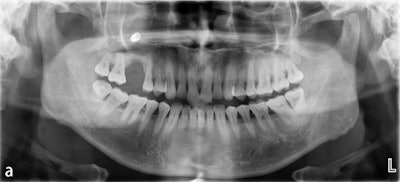

A cone-beam computed tomography (CBCT) scan of his mouth revealed that the implant was not well osseointegrated with the bone. There was also chronic inflammation in the maxillary sinus. The next day, the defective implant was removed.

Figure 2 (a-c): Cone-beam computed tomography (CBCT) scans taken at the initial consultation showed partial entry of the implant into the maxillary sinus, incomplete

osseointegration, inflammation in the maxillary sinus, and the implant crown

connecting with the neighboring tooth without a gap, (a) coronal view, (b) sagittal view, and (c) axial view.